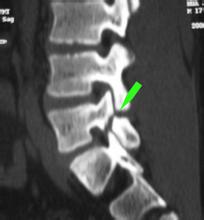

• [腰椎滑脱] 腰椎滑脱一度

导读: 一般滑脱出下一个椎体的1/4为一度滑脱,一半为二度滑脱,正常情况下应该有腰椎管狭窄,二度及以上可以造成明显的椎管狭窄,椎管狭窄容易造成神经损伤。下面;来看看腰椎滑脱一度的介绍。